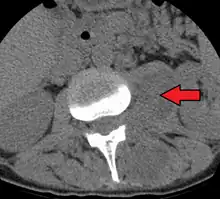

Psoas muscle abscess

Paraspinal abscess in the psoas muscle

Psoas abscess is a collection of pus (abscess) in the iliopsoas muscle compartment.[1][2] It can be classified into primary psoas abscess (caused by hematogenous or lymphatic spread of a pathogen) and secondary psoas abscess (resulting from contiguous spread from an adjacent infectious focus).[2]

Psoas abscess may be caused by lumbar tuberculosis, vertebral osteomyelitis, and pyelonephritis. Patients with Crohn's disease, diabetes, or immunocompromised states are at a higher risk of developing a psoas abscess.

Symptoms include flank pain, fever, and an inguinal mass. A positive psoas sign should raise suspicion of psoas abscess as a possibility. Owing to the proximal attachments of the iliopsoas, such an abscess may drain inferiorly into the upper medial thigh and present as a swelling in the region. The sheath of the muscle arises from the lumbar vertebrae and the intervertebral discs between the vertebrae. The disc is more susceptible to infection, from tuberculosis and Salmonella discitis. The infection can spread into the psoas muscle sheath.[3]